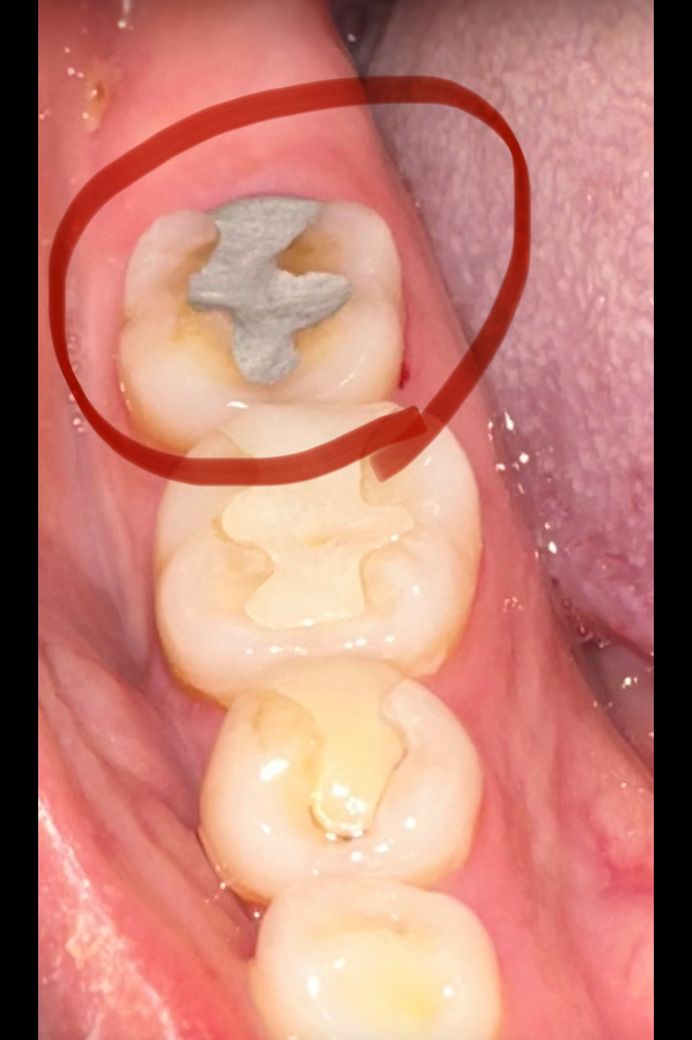

아말감으로 떼운 후 통증 질문 드립니다 전문가분들 답변 부탁드립니다 ㅠㅠ

원래 아래쪽 어금니 금으로 떼웠는데 그게 떨어져서 8월 6일날 기존에 다녔던 치과말고 다른 치과 방문 하였어요 다시 붙일려니 안맞아서 오래된 치과라 보험 적용 되는 아말감으로 떼워주셨습니다 이빨을 긁어내서 그런지 씹을때 통증 심하고 바로 위에 윗 어금니가 크라운으로 덮어 씌웠는데 그거랑 부딪혀서 그러는건지 말 하다가도 부딪히면 찌릿 합니다 이빨을 긁어내서 이런건가요? 조금 더 지켜봐도 괜찮은걸까요? ㅠㅠ 이틀 지났지만 여전히 통증은 씹을때 심하네요.. 말도 안하고 가만히 있으면 안아픕니다 눌러보면 아프기도 해요 전문가분들 도와주세요 ㅠㅠ

• 1번 째 사진